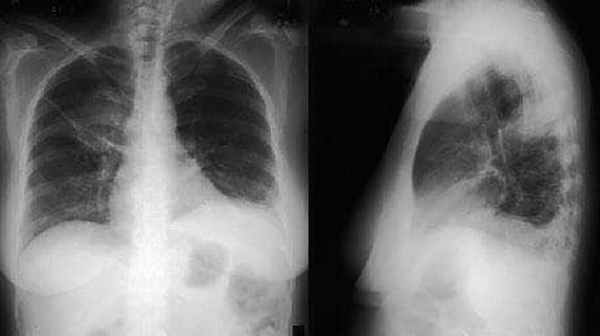

При рентгенографии органов грудной клетки выявлено усиление и сгущение легочного рисунка в прикорневых отделах с обеих сторон.

Рентгенография органов грудной клетки: в легких патологических изменений не выявлено.

При рентгенографии грудной клетки часто выявляют транзиторные пятнистые легочные инфильтраты.

При проведении рентгенологического исследования легких может не обнаруживаться никаких изменений (примерно у 25% пациентов) ; характерно обнаружение легочных инфильтратов, которые могут быть преходящими. Кавитация встречается редко. В некоторых случаях отмечается наличие плеврального выпота.